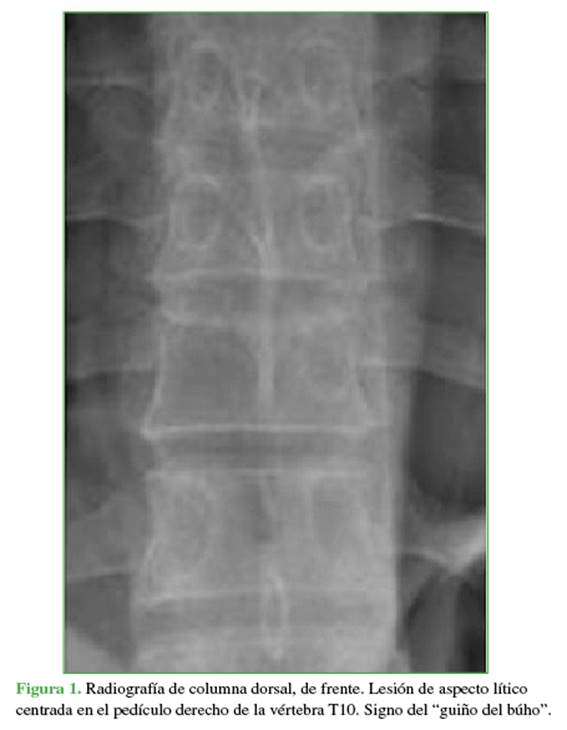

Al ingreso se solicitaron estudios por imágenes. La radiografía evidenció el signo del “guiño del búho” a nivel de la décima vértebra torácica (T10) (Figura 1).

La tomografía computarizada mostró una imagen lítica expansiva, con rotura de la cortical, que comprometía el pedículo, la apófisis transversa, el arco posterior a predominio derecho y el cuerpo de T10 (<50%) (Figura 2).